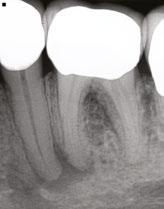

Figure 4 (left): Preoperative image of tooth No. 15. Figure 5 (right): Postoperative image. Rotary negotiation with Roto-reciprocation in all 3 canals with lengths from 25-28 mm and the ProTaper Ultimate Slider advanced to WL within 2 passes